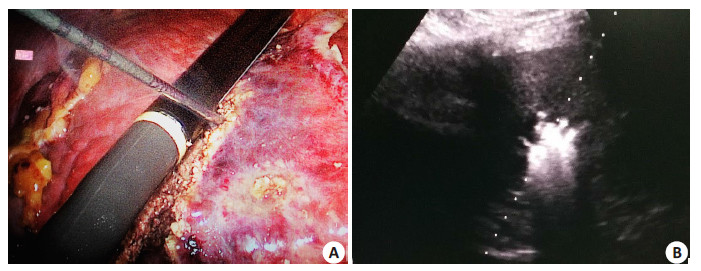

2.2 并发症LRFA组1例继发少量出血,2例继发胆漏,保守治疗好转。30例患者均出现不同程度的转氨酶升高,8例患者术后少量腹水形成,6例位于膈顶区患者出现反应性胸腔积液,LRFA组无严重并发症。PRFA组出现1例肿瘤破裂出血、1例严重胆管损伤等严重并发症,两组严重并发症发生率差异有统计学意义(P < 0.05)。两组术中消融见图 1。

图 1 射频消融治疗肝癌术中情况 Figure 1 Intraoperative radiofrequency ablation for hepatocellular carcinoma. A: Laparoscopic radiofrequency ablation; B: Pereutaneous radiofrequency ablation. |